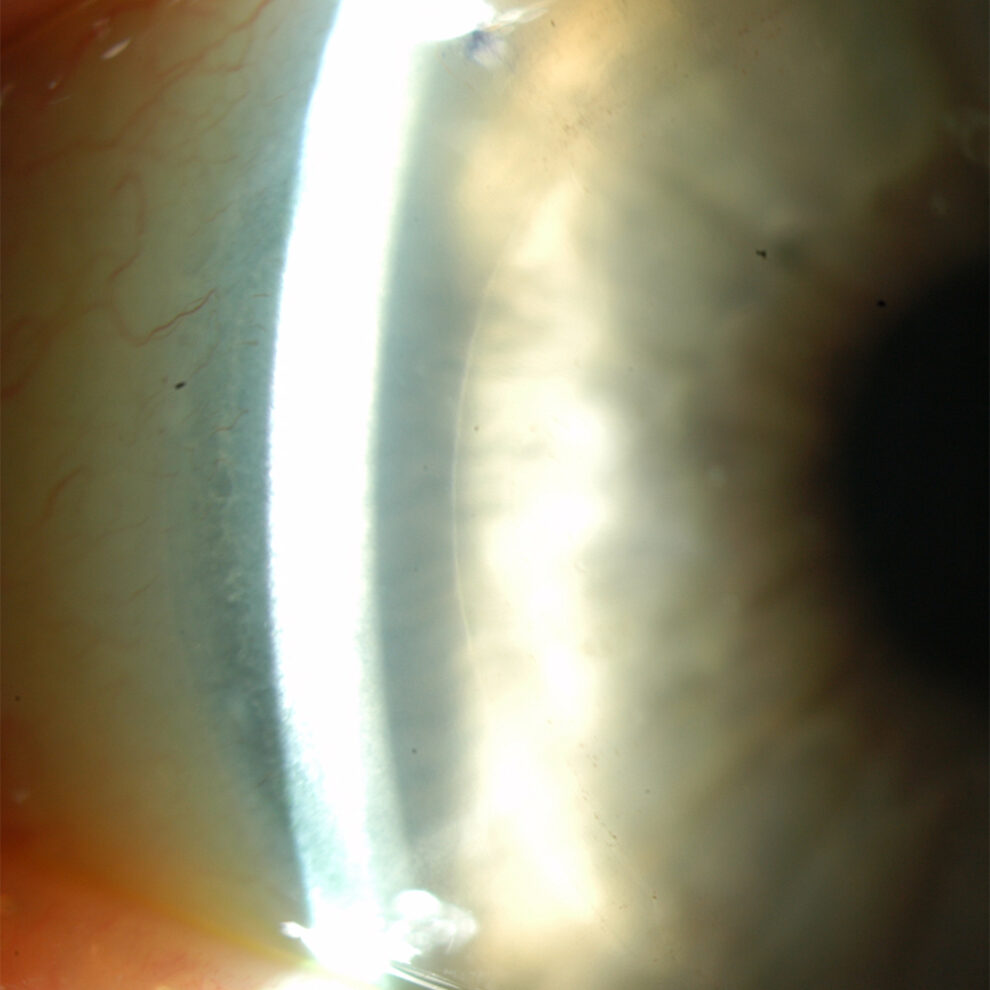

The next images show DSAEK and DMEK transplants. Notice how easy it is to see the DSAEK transplant in the eye, because it has a layer of stroma with it.  DMEK is almost impossible to see unless it is not fully attached yet.  This image of a partially separated DMEK is shown here just so that you can appreciate how thin the graft is when no stroma is transplanted.  You can see how important these grafts are to the cornea, because any area that doesn’t have the graft attached will swell thicker than other areas of the cornea.

This DMEK transplant can only be seen with special lightning techniques.